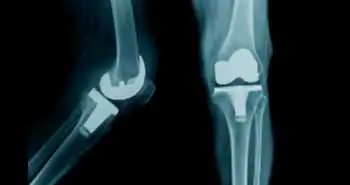

Efficacy of nomogram to predict perioperative blood transfusion risk in patients undergoing total knee arthroplasty

The preoperative predictors of transfusion risk in patients after TKA has been explored and preoperative nomogram for predicting transfusion risk has been developed in this study.